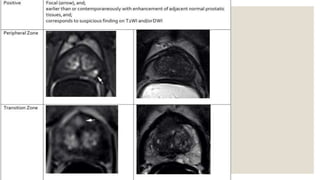

◦ Dynamic contrast enhancement (DCE)

◦ negative: no early enhancement, or diffuse enhancement not corresponding to a focal finding

on T2 and/or DWI or focal enhancement corresponding to a lesion demonstrating features of

BPH on T2

◦ positive: focal, and earlier than or contemporaneously with enhancement of adjacent normal

prostatic tissues, and corresponds to suspicious finding on T2 and/or DWI